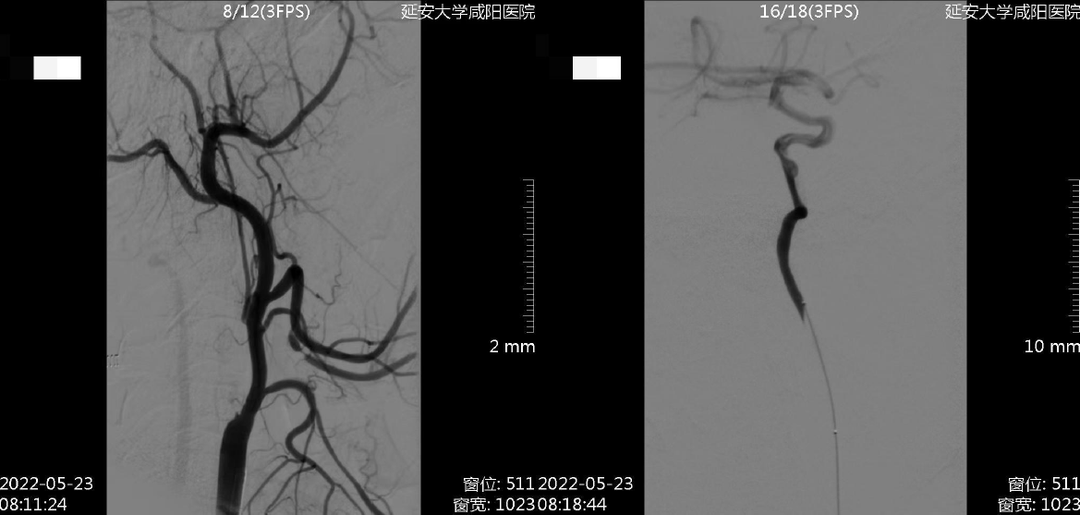

术前检查

病历夹什么径技·第152期|串联营病历夹:川陕大营_https://www.jmylbn.com_新闻资讯_第59张

病历夹什么径技·第152期|串联营病历夹:川陕大营_https://www.jmylbn.com_新闻资讯_第60张

病历夹什么径技·第152期|串联营病历夹:川陕大营_https://www.jmylbn.com_新闻资讯_第61张

<<滑动查看下一张图片>>

初步诊断:1.脑梗死(右)急性期2.右侧颈内动脉起始部次全闭塞3.右侧大脑中动脉M1段血栓形成

手术过程

1、8F导引导管到位后造影,见右侧颈内动脉起始部闭塞,微导丝及微导管穿过闭塞端,微导管造影确认真腔后,交换出微导管。

病历夹什么径技·第152期|串联营病历夹:川陕大营_https://www.jmylbn.com_新闻资讯_第62张

2、将BostonScientificSterlingMR2.5*20mm球囊置于右侧颈内动脉起始部,将压力打至8个大气压。

病历夹什么径技·第152期|串联营病历夹:川陕大营_https://www.jmylbn.com_新闻资讯_第63张

3、小球囊扩张后见右侧颈内动脉起始部重度狭窄,右侧大脑中动脉分叉处血栓形成。

病历夹什么径技·第152期|串联营病历夹:川陕大营_https://www.jmylbn.com_新闻资讯_第64张

4、使用6F中间导管抽吸后,右侧大脑中动脉血流通畅。

病历夹什么径技·第152期|串联营病历夹:川陕大营_https://www.jmylbn.com_新闻资讯_第65张

病历夹什么径技·第152期|串联营病历夹:川陕大营_https://www.jmylbn.com_新闻资讯_第66张

5、保护伞到位后,使用BostonScientificSterling MR4.0*30mm球囊扩张,将压力打至14个大气压,造影见右侧颈内动脉起始部狭窄扩张满意。

病历夹什么径技·第152期|串联营病历夹:川陕大营_https://www.jmylbn.com_新闻资讯_第67张

6、右侧颈内动脉起始部置入Carotid WALLSTENT7*40mm自膨式支架,造影见:支架贴壁良好,斑块完全覆盖,血流通畅,管腔打开良好,右侧大脑中动脉血流通畅。支架置入后观察30分钟,支架内血流通畅。